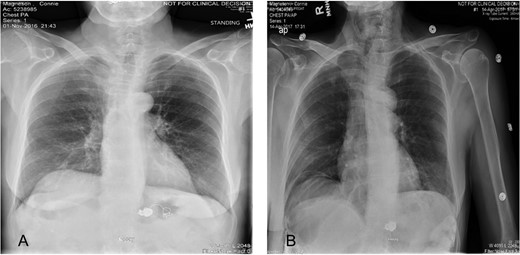

(A) Plain abdominal radiograph comparing preoperative migrated coil into the stomach. (B) Postoperative film showing coil successfully retrieved.